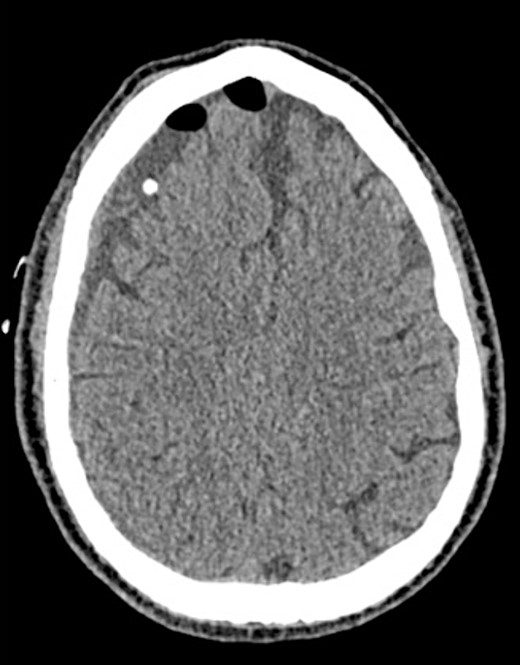

A 60-year-old male with cSDH presented to a Level I trauma center with lethargy, headaches, and left-sided hemiparesis. CT demonstrated thickened membranes and midline shift (Fig. 1).

An AR system was used to register the patient’s 3D anatomy onto the patients’ head (Fig. 2). Burr hole locations were annotated onto the registered 3D model to assist with craniotomy planning. Visualization of the 3D model confirmed plans for safe burr hole placement away from the dural venous and bony sinuses for a right frontoparietotemporal craniotomy. The AR headset was used once again to visualize the hematoma, vascular structures, and to confirm proper burr hole locations. The evacuation of the subdural hematoma was performed. Eight burr holes were placed, and a 14 × 11 cm bone flap was elevated to access the dura. The dura was then opened in a curvilinear fashion and hinged over the superior sagittal sinus. The cSDH was identified by its thick parietal and visceral membranes and underlying liquefaction, and these anatomic layers correlated directly with the AR overlay. The membranes of the hematoma were resected with the cortex demonstrating no gross abnormalities. The wound was irrigated, and the dura was closed primarily. The bone flap was then secured with two central tack-up structures followed by titanium reconstruction with multiple burr hole covers. There were no intraoperative complications, and the patient tolerated the procedure well with improved strength and decreased headache postoperatively. Post-operative CT showed interval decrease in the mixed-density subdural collection and reduced midline shift (Fig. 3).